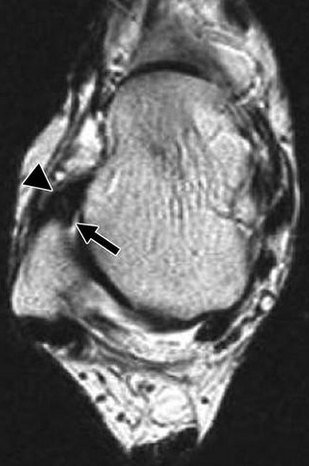

In os trigonum syndome, in the absence of an obvious os trigonum, what may be another cause?

scar tissue behind posterior talus (where the os should be)

Found on MRI